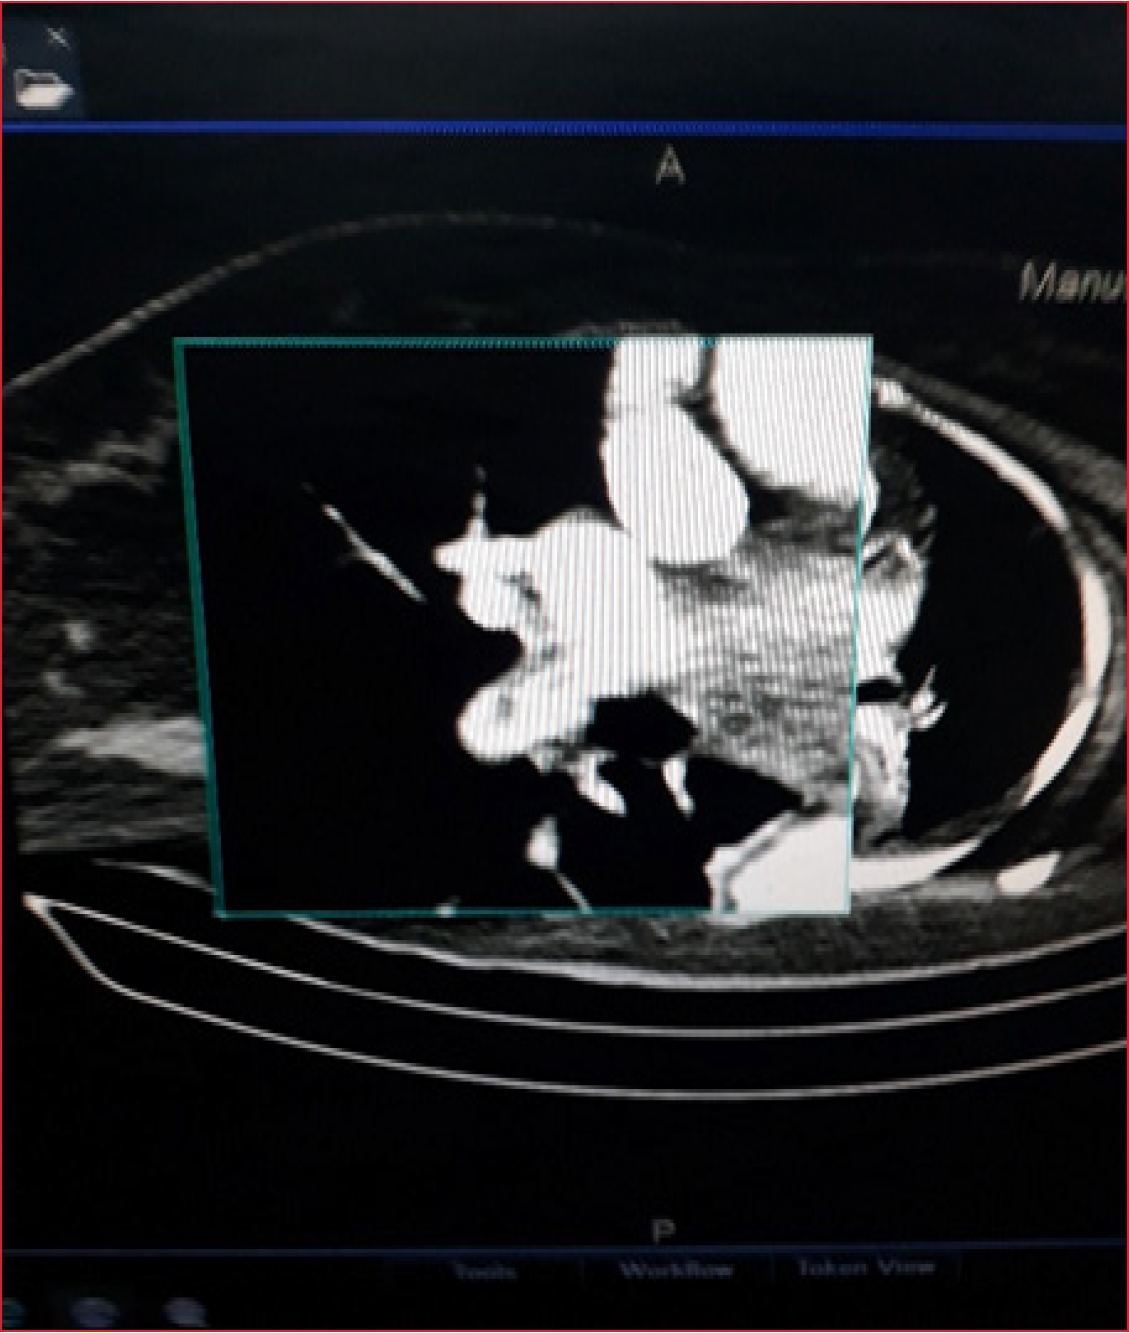

La TC de tórax mostró un tromboembolismo pulmonar parcial de la arteria pulmonar derecha y lesiones inflamatorias en ambas bases pulmonares (Figura 2).

Figura 2. Tomografía computarizada de tórax con contraste intravenoso. Tromboembolismo parcial de la arteria pulmonar derecha.

En una ecografía Doppler de miembros inferiores, se observó una trombosis venosa profunda en la pierna derecha (poplíteo).

Tras la mejoría inicial, la paciente experimenta una reagudización de la hipoxemia a los 14 días de evolución, por lo que se realiza una angiotomografía que reveló un tromboembolismo pulmonar secundario a la trombosis venosa profunda diagnosticada mediante ecografía Doppler.